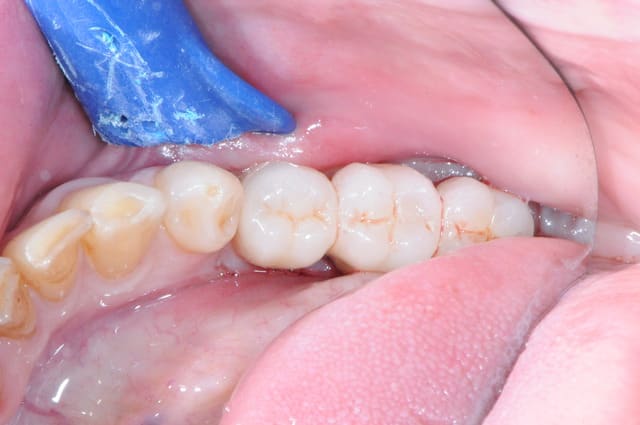

1-2

enfin, mise en place d'une membrane péricarde Jason de 30*50 (je crois)

3- j'ai profité de la stabilité de la mesh comme piquet de tente pour bourrer la cavité avec du MAXGRAFT (os humain)..

4-5- un peu de A-PRF (the king !)

6- le plus important des sutures hermétiques et une gencive immobile en fin d'intervention

7 les radios post-op